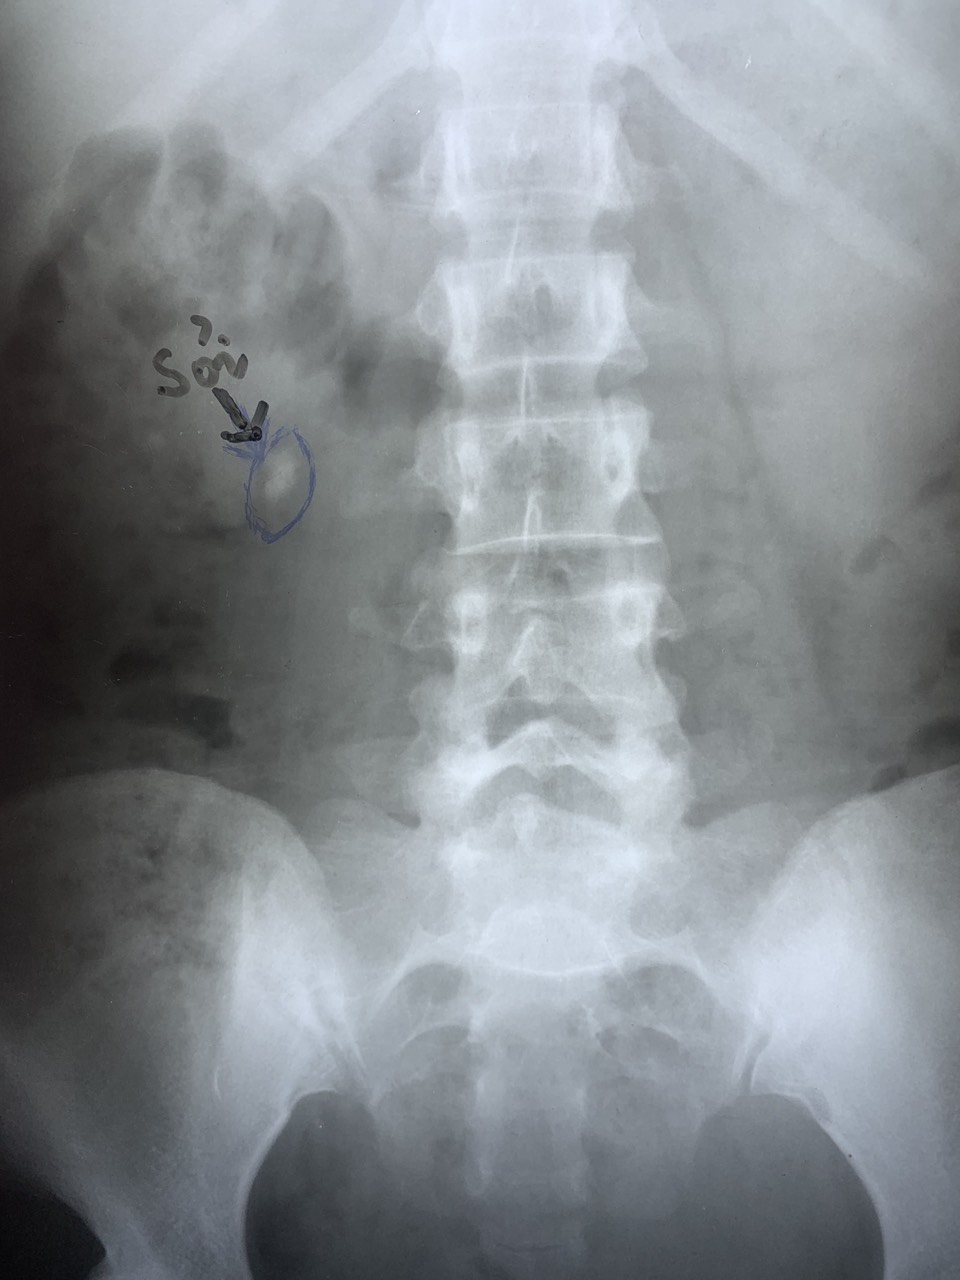

Hình ảnh siêu âm và chụp Xquang